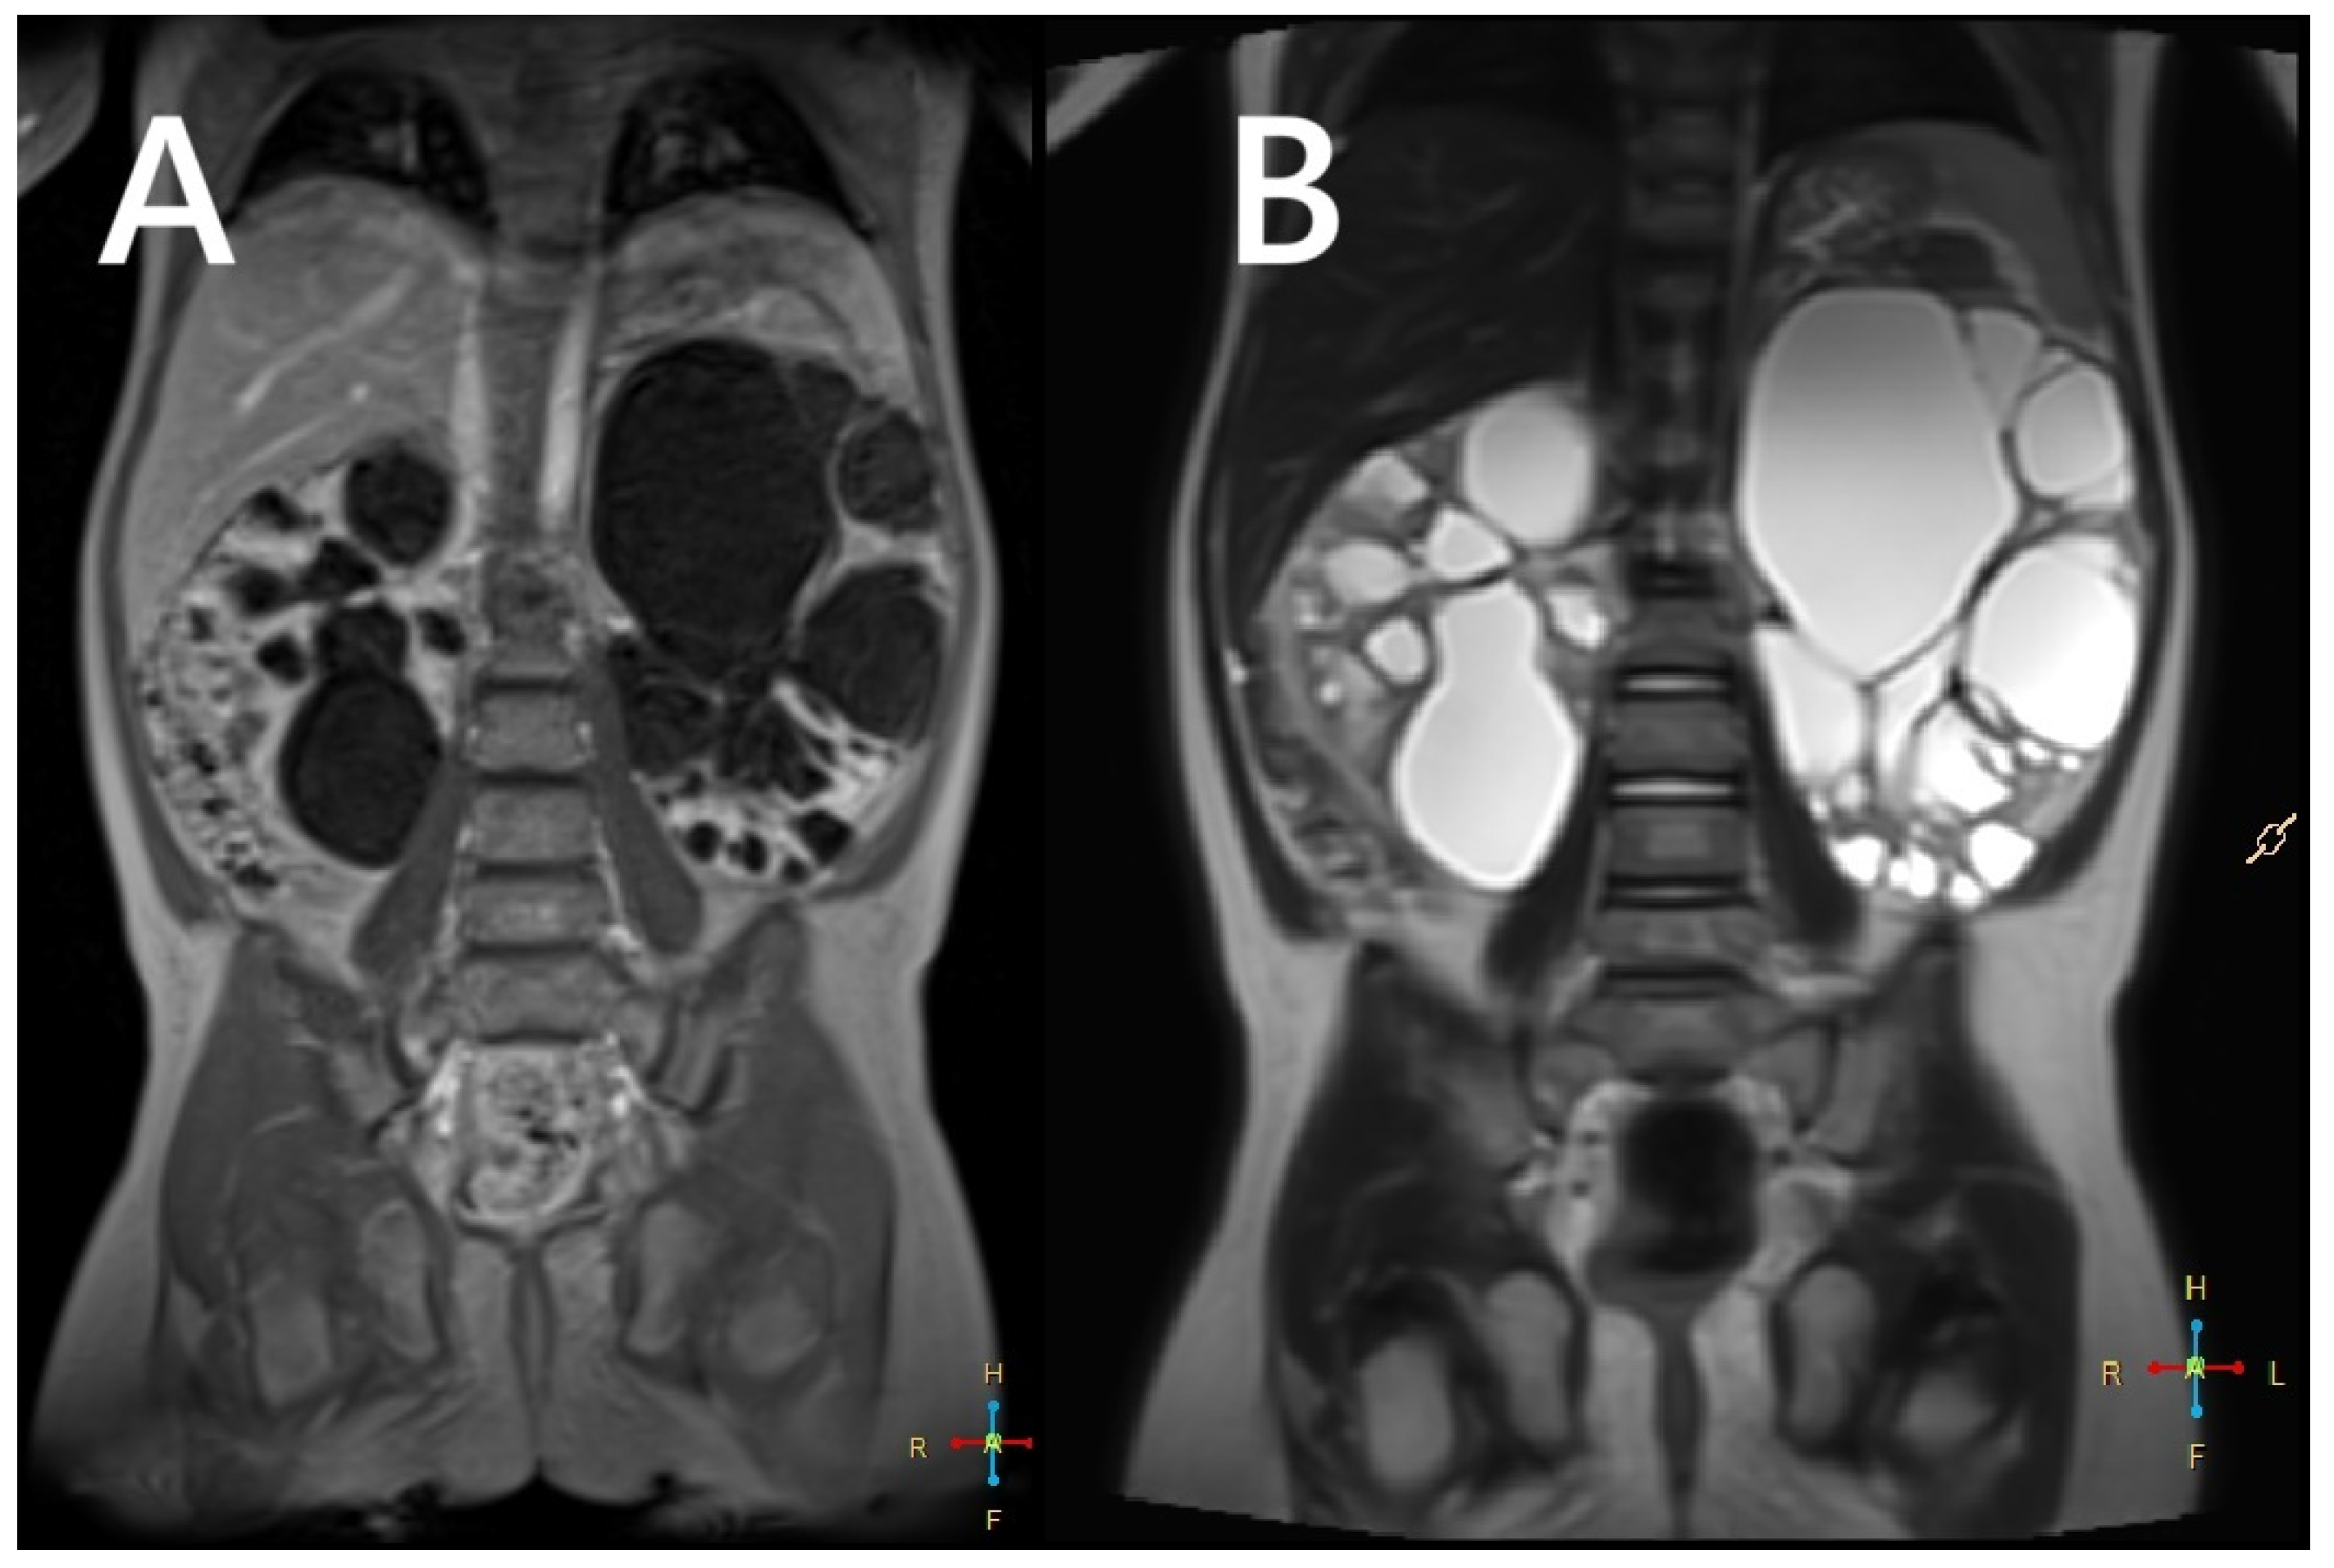

In 2–3% of patients with TSC, TSC2/PKD1 contiguous gene syndrome (CGS) is found as a distinct disease entity with clinical features typical of TSC combined with severe and early polycystic kidney disease, almost always associated with early progression to end-stage renal disease (Figure 3). The TSC2 and PKD1 genes lie in a slightly overlapping tail-tail position on the short arm of chromosome 16 (16p13.3), and the cause of the disease is a large deletion involving the 3′ end of TSC2 and extending to the neighbouring PKD1, encoding polycystin-1. There appears to be a spectrum of variability in disease severity and prognosis for CGS, reflecting allelic variation and tissue mosaicism.

As with ADPKD, subtle cortical hyperechogenicity and renal enlargement may be evident on prenatal ultrasound in patients with CGS. Similarly, an infant or young child with TSC who presents with hypertension associated with enlarged, cystic kidneys may also have CGS. In milder cases, only genetic testing can distinguish the polycystic TSC phenotype from the CGS phenotype [23]. In addition to the potentially severe cystic phenotype, patients with CGS are also predisposed to developing renal masses due to TSC2 mutations. These masses present the same challenges as in TSC patients without PKD1 mutations. Consequently, renal imaging in CGS should follow the stricter TSC guidelines, recommending annual MRI or CT, rather than the protocols used for ADPKD [24].

Figure 3. An MRI without (A) and with a contrasting agent (B) of a 3-year-old boy with a contiguous gene deletion syndrome involving TSC2/PKD1. Both kidneys are markedly enlarged, containing numerous thin-walled cysts of varying shapes. The remaining renal parenchyma is severely deformed.